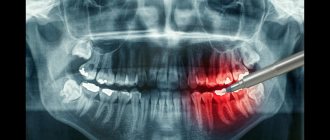

Panoramic shot

A dental panoramic photograph is a circular digital image of the entire jaw in a two-dimensional plane.

This examination allows you to:

• identify hidden caries;

• diagnose the condition of teeth under crowns and fillings;

• assess the health of canals and root tips;

• determine the presence of permanent tooth buds in children;

• establish periodontitis disease;

• monitor the condition of teeth during implantation and prosthetics.

An orthopantomogram, like a dental photograph, significantly increases the capabilities of dentists and allows them to see what cannot be detected during a visual examination.